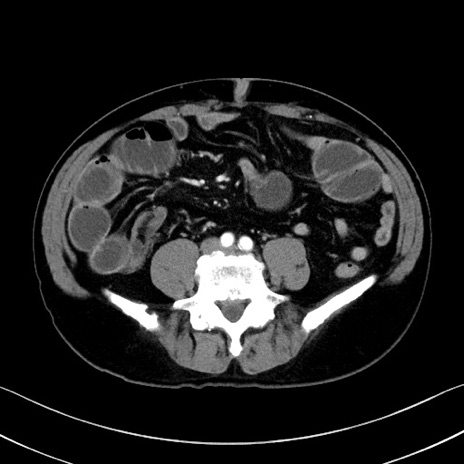

症例35(横断像)

【症例】70歳代 男性

【主訴】腹部膨満、嘔吐

【現病歴】昨日より腹部膨満感出現。本日増悪し、仙痛出現。嘔吐あり、受診。

【既往歴】糖尿病、胆摘後

【身体所見】BP 149/80mmHg、HR 74/min、BT 35.9℃、腹部:膨満、軟、圧痛なし。腸雑音減弱あり。上腹部正中切開瘢痕あり。

【データ】WBC 13500、CRP 1.72